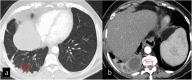

Hydatid cyst caused by the larval form of Echinococcus is a worldwide zoonosis. The lungs and liver are the most common sites involved. While the lung parenchyma is the most common site within the thorax, it may develop in any extrapulmonary region including the pleural cavity, fissures, mediastinum, heart, vascular structures, chest wall, and diaphragm. Imaging plays a pivotal role not only in the diagnosis of hydatid cyst, but also in the visualization of the extent of involvement and complications. The aim of this pictorial review was to comprehensively describe the imaging findings of thoracic hydatid cyst including pulmonary and very unusual extrapulmonary involvements. An outline is also given for the findings of complications and differential diagnosis of thoracic hydatid cyst.